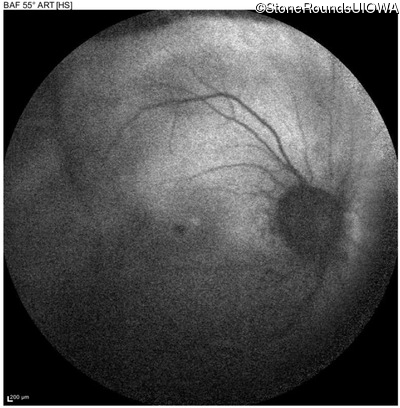

Autosomal Dominant Vitreoretinochoroidopathy (III4A)

Age at visit: 47 years

OD OS

This 47 year old woman began wearing glasses at age 5 and had cataract surgery at age 32. At that time her doctor noticed a retinal abnormality.